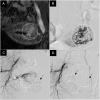

Interventional radiology is continuing to reshape current practice in many specialties of clinical care and the fields of gynecology and obstetrics are no exception. Imaging skills, clinical knowledge as well as vascular and non-vascular interventional technical ability, are essential to practice interventional radiology effectively. Patient safety is of paramount importance in interventional radiology as in all branches of medicine. Potential failures occur throughout successful procedures and are attributed to a spectrum of errors, including equipment unavailability, planning errors, and communication errors. These are mainly preventable by improved preprocedural planning and teamwork. Of all the targeted and effective actions that can be undertaken to reduce adverse events, the use of safety checklists might have a prominent role. The advantage of a safety checklist for interventional radiology is that it guarantees that human error in terms of forgetting key steps in patient preparation, intraprocedural care, and postoperative care are not forgotten.

Figures